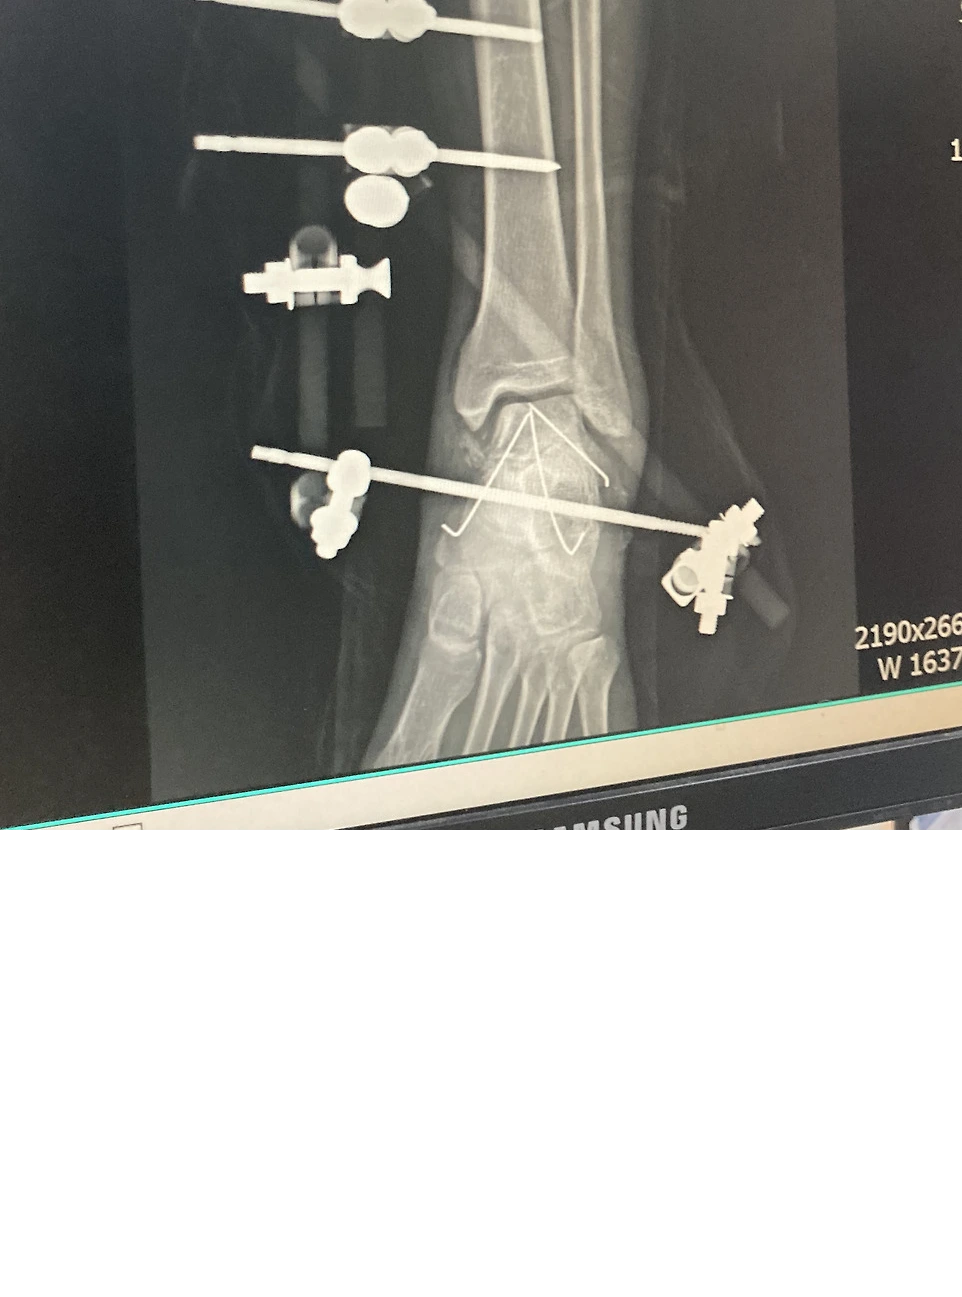

수술 들어가기 전 간단한 설명을 해주시긴 하셨는데 어려운 용어가 있어서 잘 이해는 가지 않았다. K강선을 이용해서 부러진 뼈가 움직이지 않게 고정한다고 간단하게 이해를 했다. 수술실에 들어서자 차가운 공기가 느껴졌다. 왠지 모르게 수술실의 분위기가 싫었다. 수술 침대에 눕고 마취과 선생님이 오시더니 내 등을 새우처럼 굽히게 하고 옆으로 눕게 했다. 척추마취였다. 척추가 딱금 거리더니 허리 밑 부분의 감각이 사라졌다. 허리 밑 부분은 바늘로 찔러도 느낌이 없었다. 그리곤 곧 잠이 들었다. 수술은 6시간 정도진행 되었다.

수술 후 의식이 돌아온 나는 깜짝 놀랄 수밖에 없었다. 철제 봉과 나사들이 내 다리에 박혀 있었다. 수술 중 의식이 없어 무슨 일이 일어났는지 모르니 더욱 두려운 감정이 밀려왔다. 미리 설명은 들었지만 내 다리에 나사와 철제봉이 박혀있는 것을 직접 보니 만감이 교차했다. 나는 처음 겪는 일에 당황하여 간호사에게 여러 가지를 물어보았다. 수술이 잘 된 건가? 나사를 이렇게 박는 게 맞는 거냐? 등. 간호사는 나를 진정시키며 수술 잘 되었고 의사 선생님이 실력 있는 분이라며 나를 진정시켰다.

의사 선생님은 절대로 발을 땅에 디디면 안 된다는 처방을 내리셨다. 응급수술이기 때문에 완벽하게 고정되어있지 않아서 발을 디디면 큰일 날 수 있다고 하셨다. 그리곤 부기가 빠져야 본 수수술을 할 수 있다고 하셨다. 본 수술은 부러진 뼈에 나사를 박아서 뼈가 붙을 때까지 고정하는 수술이다. 이 수술은 발을 절개해서 열어야 하는데 수술 부위가 많이 부어 있으면 수술이 어렵다고 하셨다. 기약 없이 부기가 빠지기를 기다리며 산송장처럼 병원에서 누워 지내야 했다.

정확한 병명은 거골의 폐쇄성 분쇄골절이다. 그 당시 의사 선생님 의견으로는 다 나아도 반드시 절뚝거릴 것이라고 하셨다. 그리고 거골이라는 부위가 연골로 둘러 쌓여있어 골절 시 연골 손상도 동반할 것이고, 특히 피가 잘 안 통해 벼가 잘 붙지 않고 함몰될 수 있는 최악의 가능 성도 있다고 하셨다.